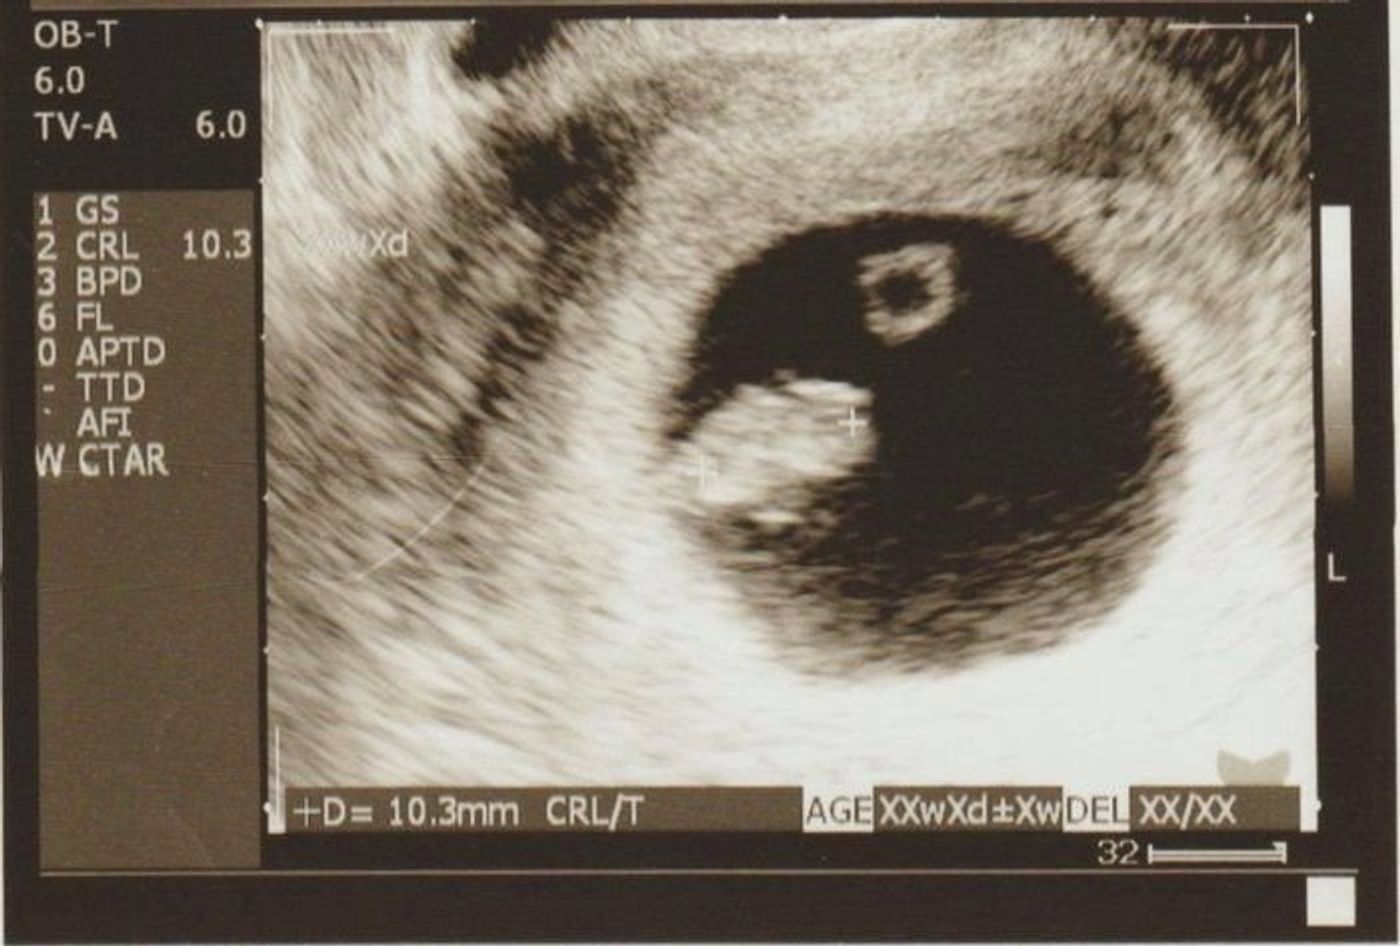

妊娠7週2日目のエコー写真 心拍確認 Crlは13 3ミリ 2頭身になりました 保育士うたのサイト

妊娠7週目赤ちゃんのエコーはどう見える? 出血があったらどうすればいい? 妊娠7週目はママのカラダにもつわりなどの変化がでてきますので、ほとんどのママは産婦人科への初診をすませているころになります。 まだ、ママのお腹の見た目 妊娠7週目になると一番気になるのは赤ちゃんのエコー写真の変化です。 心拍が確認できるようになる時期で産婦人科での診断や内容も変化し始めます。 医師からは母子手帳の申請をするようにと言われるのも妊娠7週を確認した時からになります。 この 7週0日(7w0d・男の子)|わんちゃん さん(26歳) エコー写真撮影時のエピソード: 妊娠が発覚した時、初めて撮ったエコー写真です。 当時ドキドキしながら行った婦人科で、ドラマで見たことしかなかったエコー写真を手にした時、とてもうれしい気持ちと、私が母になれるのかと

妊娠7週 赤ちゃんの心拍確認 つわりの症状や過ごし方 エコー写真付き ままのて